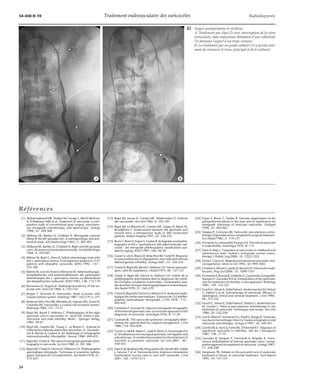

36 Technique de traitement. La sonde n’a pas pu être descendue en dessous de l’aile-ron

sacré, il a été mis en place un ressort (flèche). Puis un guide-cathéter (1) a été placé

bas de façon à compléter cette première thérapeutique par la sclérose.

37 Technique de traitement. Mise en place de deux ressorts, assez bas, dans une veine

testiculaire d’assez grande taille.

38 Technique de traitement. Très volumineuse veine testiculaire ayant incité à la

mise en place de deux ressorts de grande taille.

39 Technique de traitement. Mise en place dans deux branches pelviennes, à deux ni-veaux

différents, de trois ressorts (flèches).